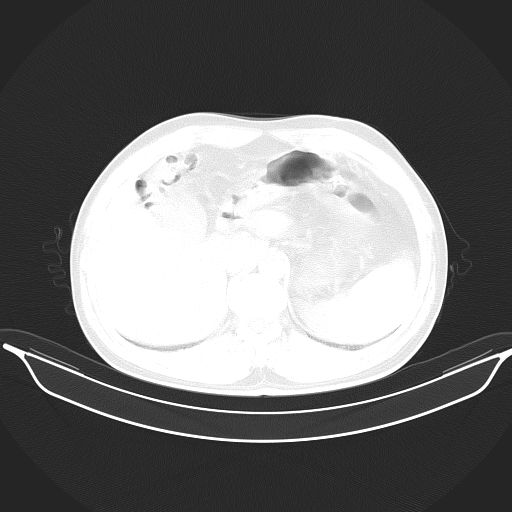

标题: CT25490:男,40岁,体检发现;无其它不适。 [打印本页]

标题: CT25490:男,40岁,体检发现;无其它不适。

考虑:1、过各敏性肺炎可能性大,建议定期复查。

2、轻度脂肪肝。